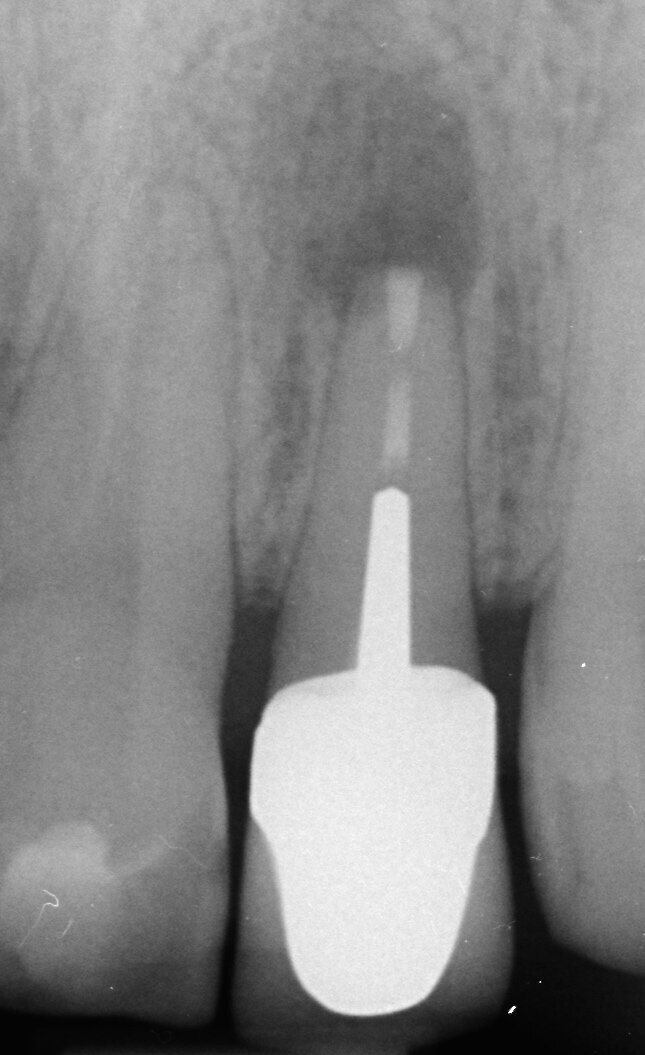

Fig. 2a: (a) Endodontically treated tooth with fistula. (b) After retreatment, the tooth showed an open apex. (c) MTA application with the MAP System and PD MTA White. Condensation of the MTA with pluggers (d) or paper points (e). (f) MTA plug. (g) Post-op radiograph showing the MTA plug and the reconstruction with a fibre post.

Fig. 2g: (a) Endodontically treated tooth with fistula. (b) After retreatment, the tooth showed an open apex. (c) MTA application with the MAP System and PD MTA White. Condensation of the MTA with pluggers (d) or paper points (e). (f) MTA plug. (g) Post-op radiograph showing the MTA plug and the reconstruction with a fibre post.

In order to prevent extrusion of root canal filling material in immature teeth with open apices, MTA is used as an apical plug. The results of many studies have shown that MTA induced apical hard-tissue formation more often and its use was associated with less inflammation than with other test materials (Figs. 2a–g).[4]